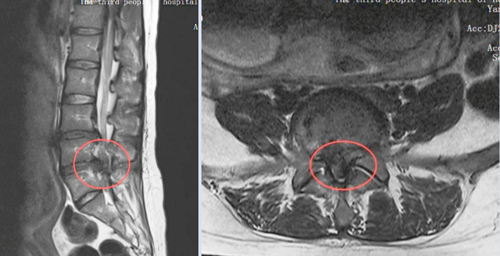

当地医院诊断后,结果令全家心弦紧绷——这不是普通的孕期不适,而是由严重腰椎间盘突出引发的“马尾神经综合征”。

这是一种急症,若不及时处理,可能导致永久性的下肢瘫痪、大小便功能障碍。更棘手的是,李女士还怀着宝宝。